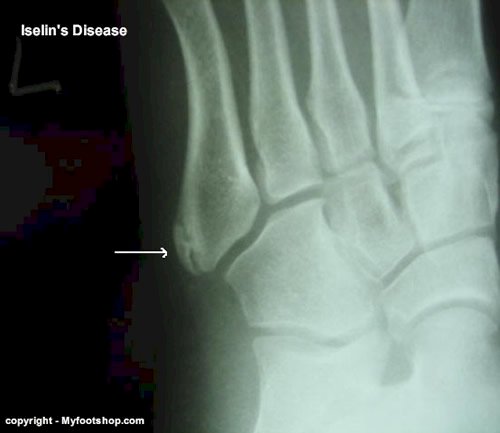

The third case was a 12 y/o male with no history of injury. He was referred to me for evaluation and treatment of a 5th metatarsal fracture. Symptoms included +1 swelling that was site-specific and pain with initial onset of activities along with pain with increased duration of activities. In this case, the primary problem was not actually a fracture but a growth plate issue called apophysitis. More specifically, apophysitis of the 5th metatarsal base is known as Iselin’s disease. Iselin’s disease is self-limiting in that the symptoms will resolve at boney maturity. Short term treatment includes limitation of activity and use of a lateral sole wedge to limit supination of the foot. Iselin’s disease is a good example of 5th metatarsal pathology specific to the epiphysis.